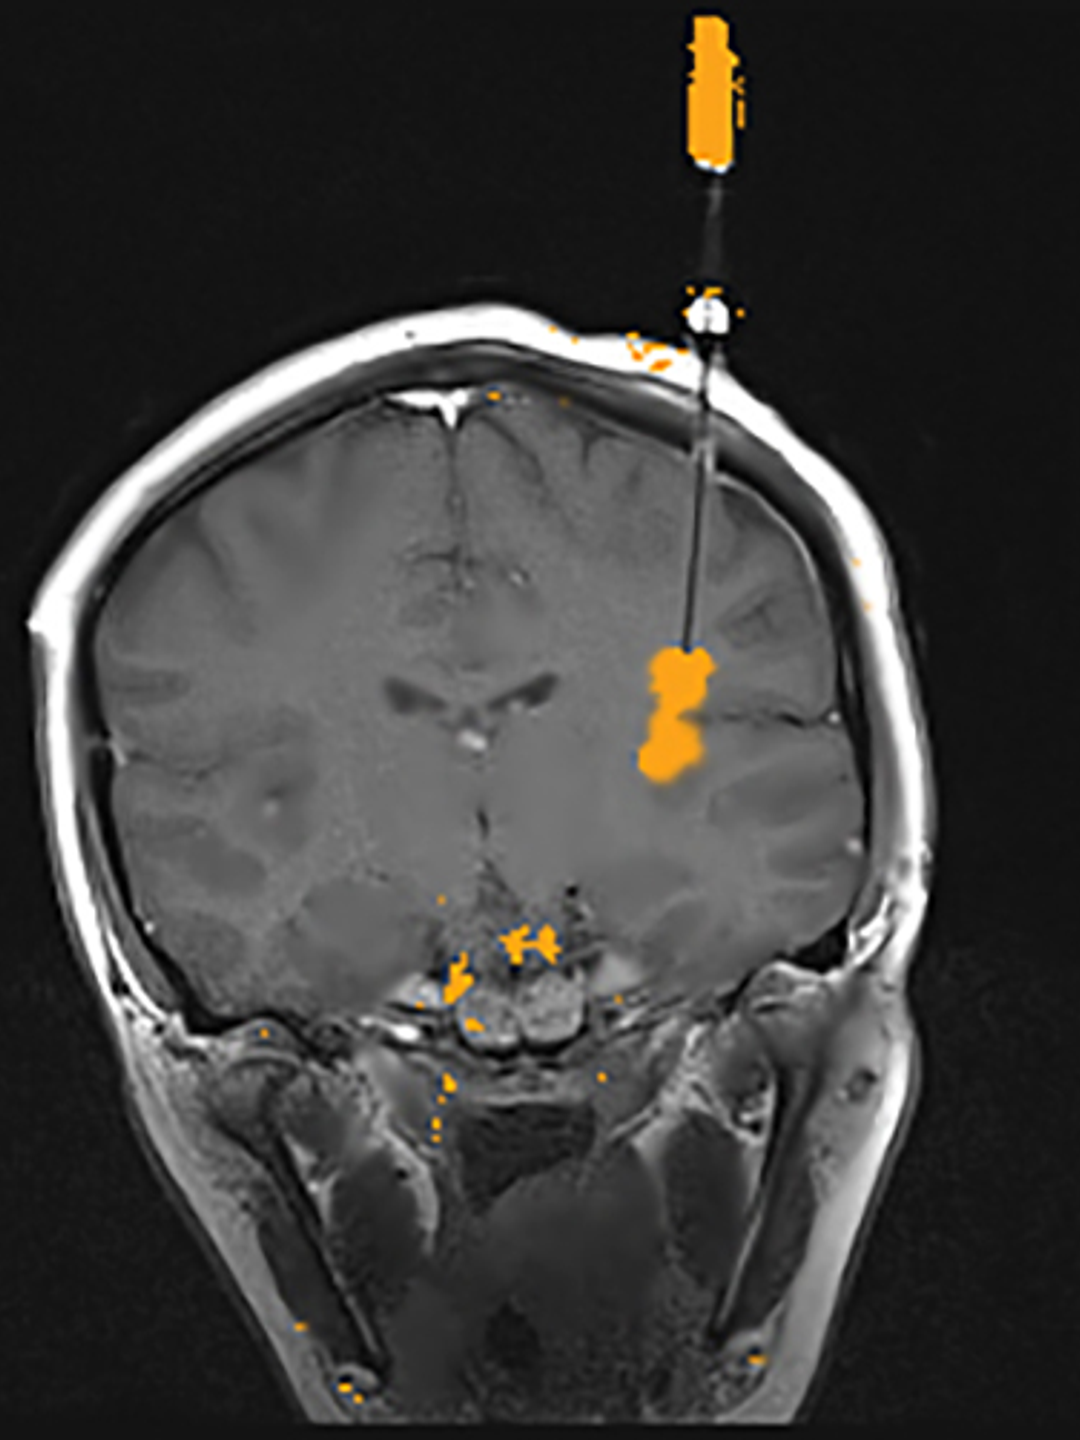

StereoEEG electrodes placed to identify the location of seizures

Figure 1: StereoEEG electrodes placed to identify the location of seizures. Each colored dot represents an individual electrode contact, an area capable of recording seizure activity. The electrode contact at the purple crosshairs was one of the primary areas from which seizures started. This part of the brain is the left posterior insula.

Given the above information and the lack of a clear lesion on the brain MRI, a stereo EEG (SEEG) evaluation was conducted to better identify the source of her seizures (Figure 1). This involved placing electrodes in targeted areas of Anna’s brain, which pinpointed the source of the seizure locus to the left posterior insula, a deeper area of the brain covered by the frontal and temporal lobes.